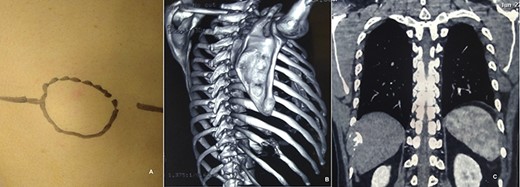

A 29-year-male presented with complain of swelling on the right posterolateral chest wall of 3-month duration associated with mild pain on and off. There was no history of trauma, and his past medical history was non-contributory. It was slowly increasing in size. His physical examination revealed a mildly tender palpable mass of tenth rib on posterolateral wall of the right chest (Fig. 5A). His all routine laboratory test results were within normal range. Chest radiograph performed showed vague lesion of right tenth rib. CT chest revealed 11 × 4 cm lytic lesion of the tenth rib involving posterolateral part (Figs 5B and C). Fine needle aspiration cytology was hemorrhagic. A right anterolateral thoracotomy was done and the mass present in posterolateral part of right 10th rib was excised (Fig. 6A). The underlying visceral pleura, lung and diaphragm were free. The mass was resected along with the adjacent parietal pleura and normal rib segment (Fig. 6B). The cut section of specimen revealed hemorrhagic material covered with thin bony shell. Histopathology confirmed the mass to be Fibrous dysplasia with aneurysmal bone cyst-like areas (Fig. 6C). His post-operative course was uneventful and discharged on 3rd post-operative day without any complaints. After 2 year of follow-up, he is doing well without any recurrence.

Mass in right posterolateral wall (A). CT chest showing lytic lesion of right tenth rib (B and C).